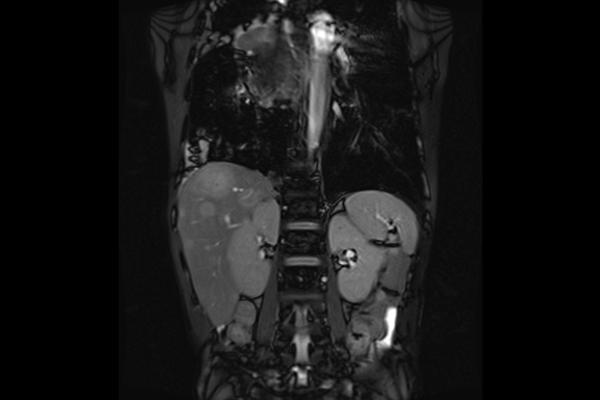

Chẩn đoán toàn thân: đầu, cổ, cột sống, khớp, bụng, tiểu khung, mạch máu

Cho phép scan tư thế linh hoạt: nằm ngửa hoặc nghiêng, thuận tiện cho nhiều loại coil